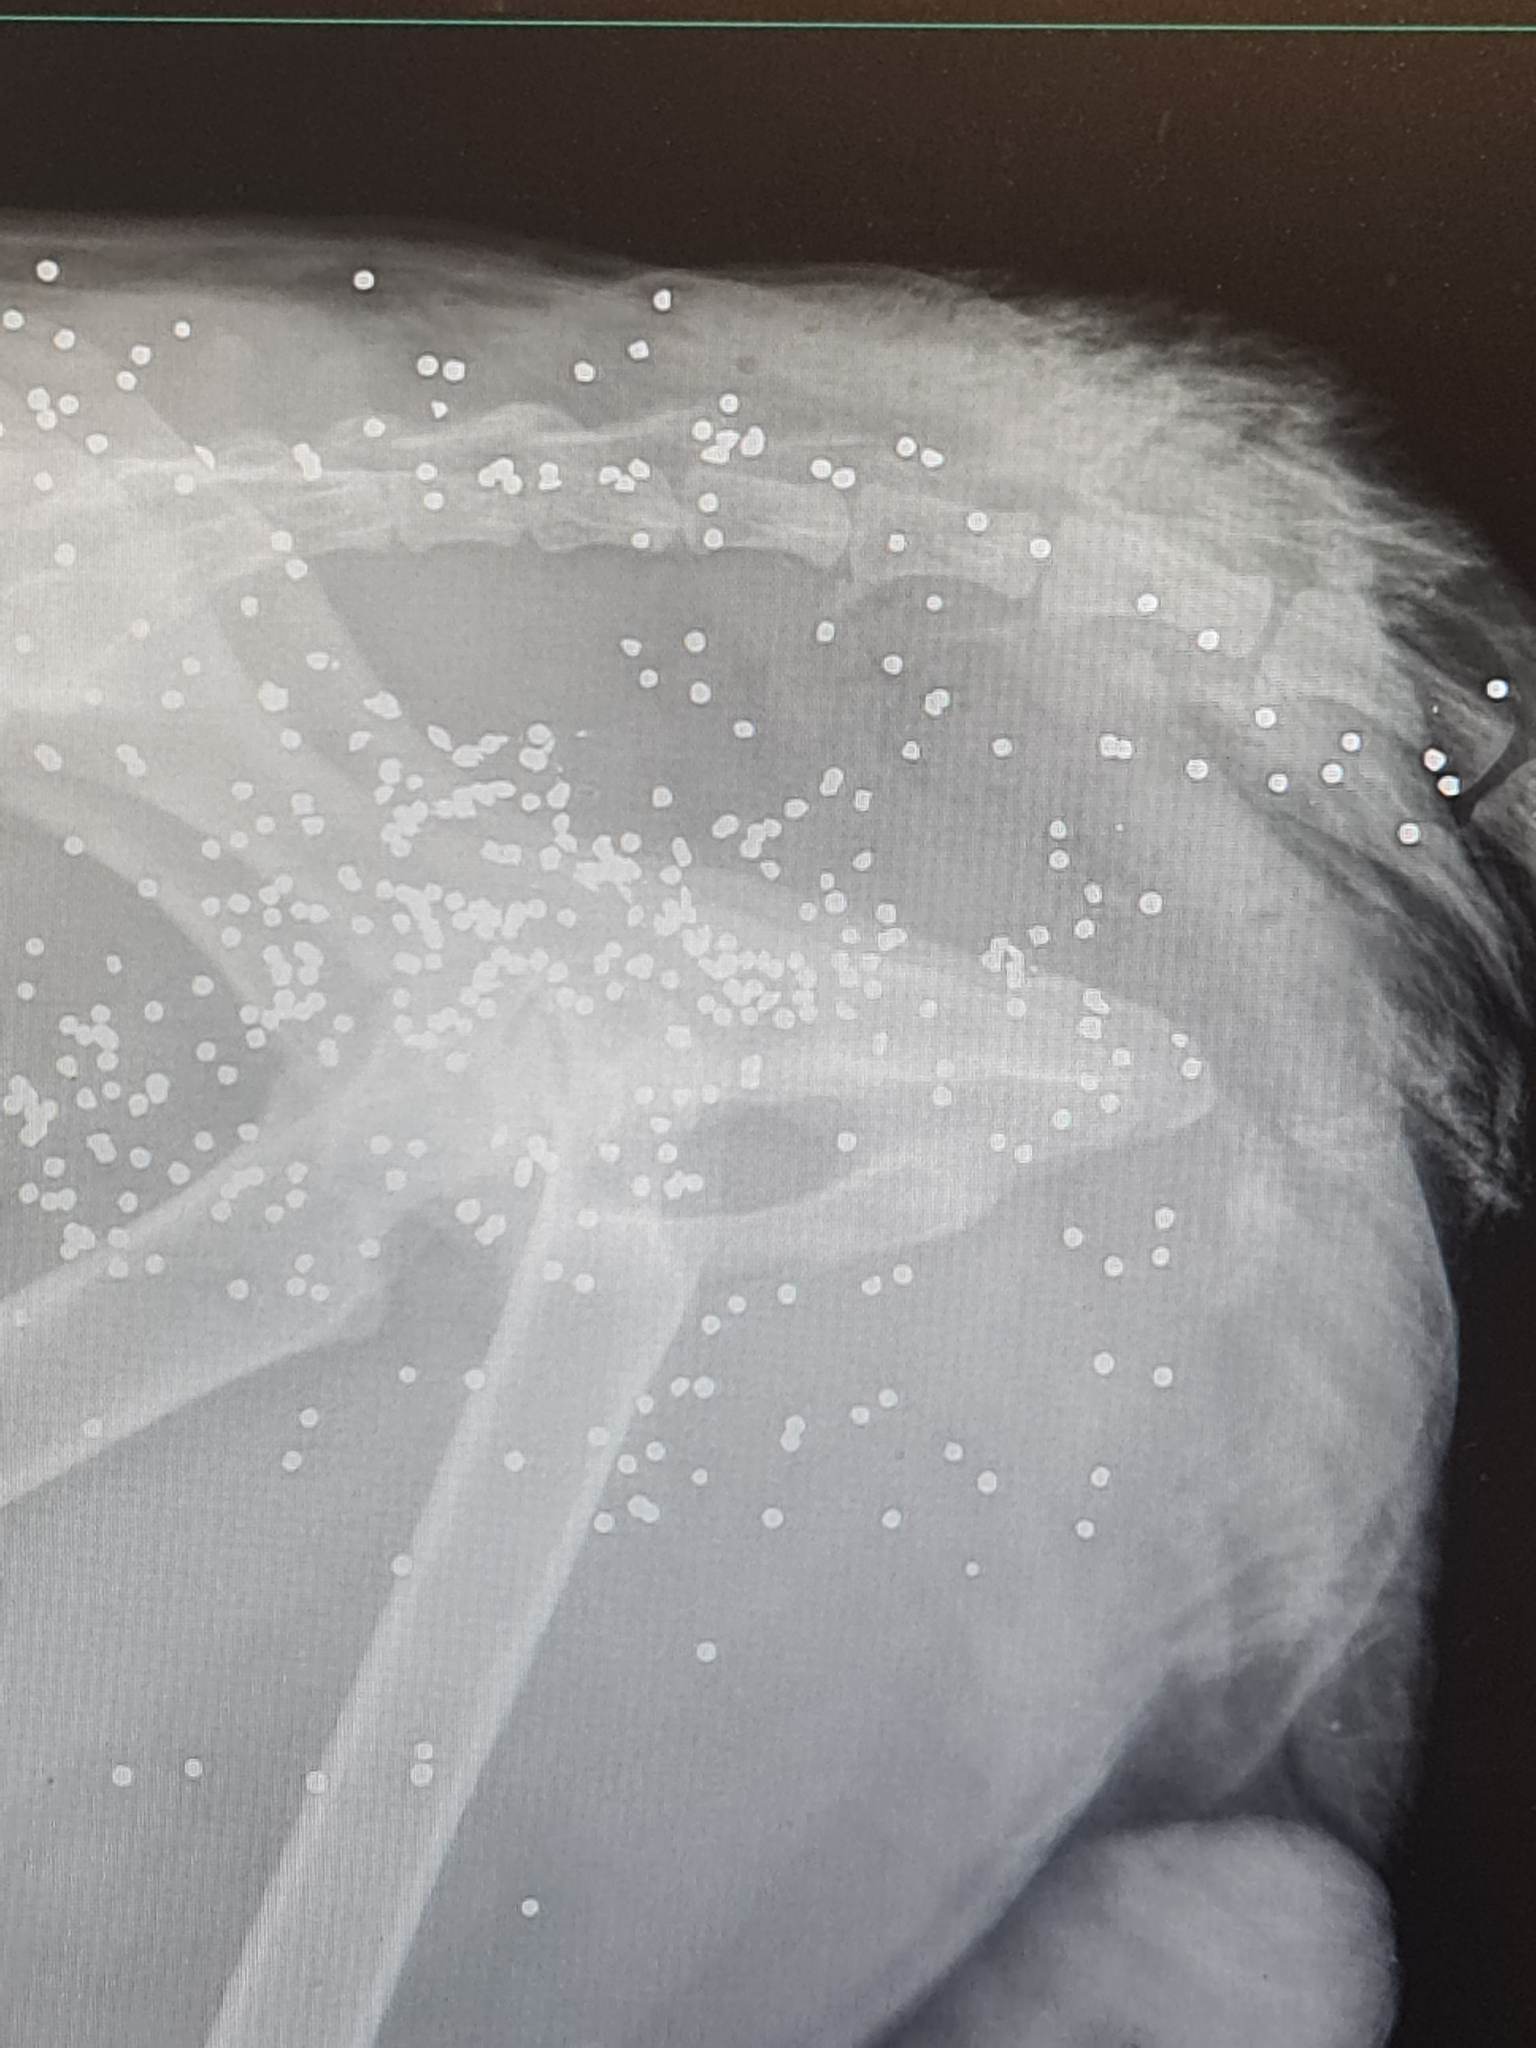

Αυτή η εικόνα αξίζει να γίνει Ίνδαλμα και Πρότυπο για τη νέα γενιά, μιας και τελικά φαίνεται πως μόνο από τους νέους έχουμε να περιμένουμε μια "Άνοιξη". Ο σκύλος, πονεμένος, απορημένος, φοβισμένος μα και εν τέλει αφημένος εντελώς σ’ αυτό που του συνέβαινε, μεταφέρθηκε στο κτηνιατρείο της Ελένης Μπαρδάκου όπου διαπιστώθηκε πως έχει πυροβοληθεί εξ επαφής κι είναι γεμάτος σκάγια.